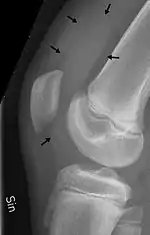

X-ray of the knee of a 12 year old male, with knee effusion extending into the suprapatellar bursa.

- the suprapatellar bursa or recess between the anterior surface of the lower part of the femur and the deep surface of the quadriceps femoris.[2] It allows for movement of the quadriceps tendon over the distal end of the femur. In about 85% of individuals, this bursa communicates with the knee joint. A distension of this bursa is therefore generally an indication of knee effusion.[3]